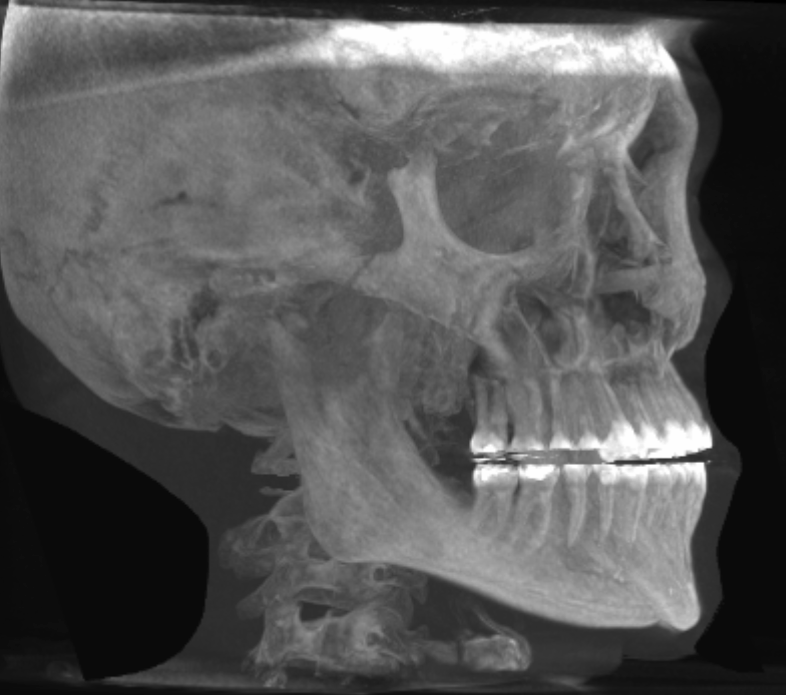

Rate this CT scan (profile, forward, 45deg)

soft tissue removed. tell me how my bones look.

narrow jaw, and kinda short chin.

you're not recessed, frankfurt plane is okay. gonions are a little bit high but not a big problem.

gonions are outward, that is really important.

is it my impression or do you got downward growth?

>is it my impression or do you got downward growth?

maybe. i have gummy smile. jaw surgeon said it seemed mostly due to soft tissue, but offered le fort 1 anyway to keep my options option. i'm tryna to decide best option and see if jaw surgery is needed for other reasons too... two birds, one stone etc